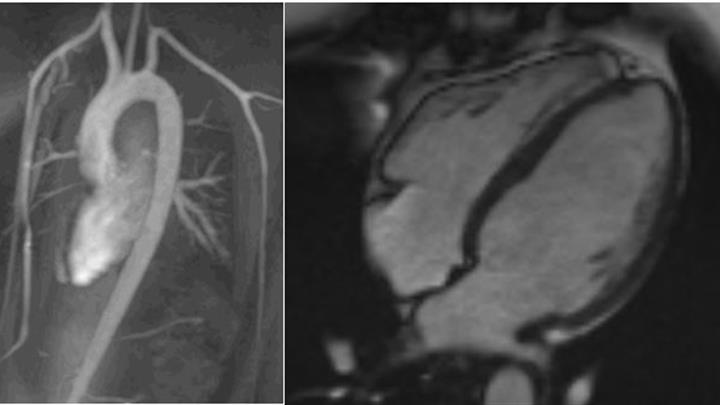

Cardiavc MRI examination is increasingly used to investigate the cause of heart disease when ultrasound and other basic examinations have not provided sufficient answers. MRI is based on signals generated by a strong magnetic field from tissues, and it offers excellent resolution for visualizing cardiac structures.

Cardiac MRI provides detailed information about the structure and function of the heart.